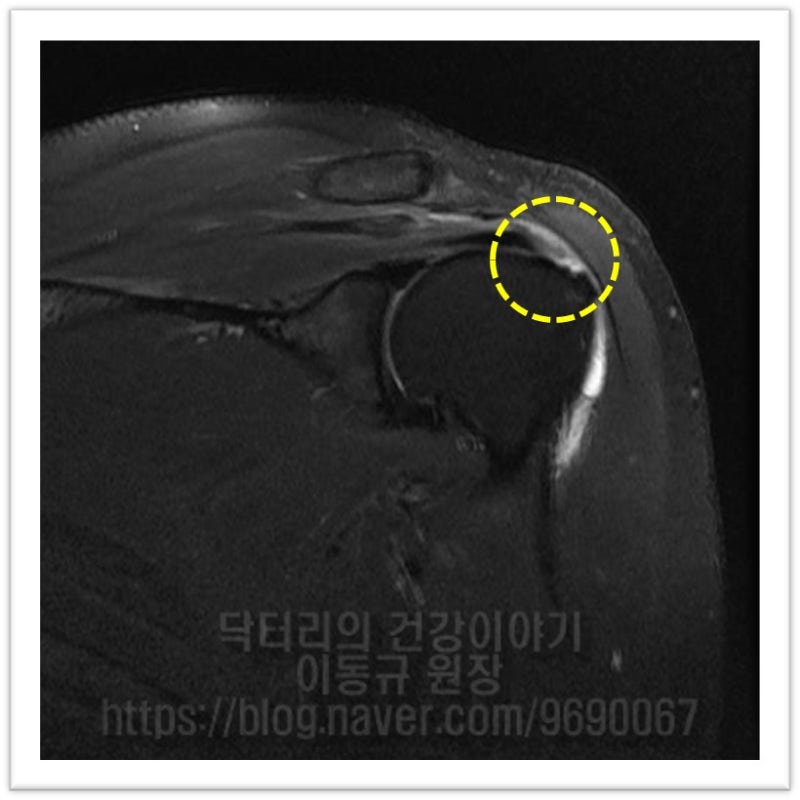

안녕하세요. 정형외과 전문의 이동규 입니다. 회전근개 파열이 오래 되면 혈류 제한이 있으면서 퇴행성 변화가 진행하게 됩니다. 이러한 경우 수술을 한다고 해서 완전히 치유되지 않을 수도 있습니다. 즉 새 천을 꼬매면 짱짱하게 봉합이 되지만 삭은 천을 꼬매면 다시 찢어질 수 있는 것과 같습니다. 회전근개 파열이 오래 된 상태라면 힘줄의 상태에 따라 보강술이 필요할 수 있습니다. 케이스를 보여드리겠습니다. 48세 여자환자 입니다. 5년전 회전근개 파열 진단을 받았으나 직장 및 개인적인 사정으로 수술을 하지 않고 아플때만 통증 주사만 맞아오던 환자였습니다. 이학적 검사상 empty can test 양성 보였고 극상근의 파열이 의심되었습니다. MRI 검사를 살펴보겠습니다.

MRI 상 파열 사이즈도 크지 않고 힘줄 상태로 그렇게 나쁘게 보이지 않습니다. 관절경을 통하여 봉합술을 하기로 하였습니다.